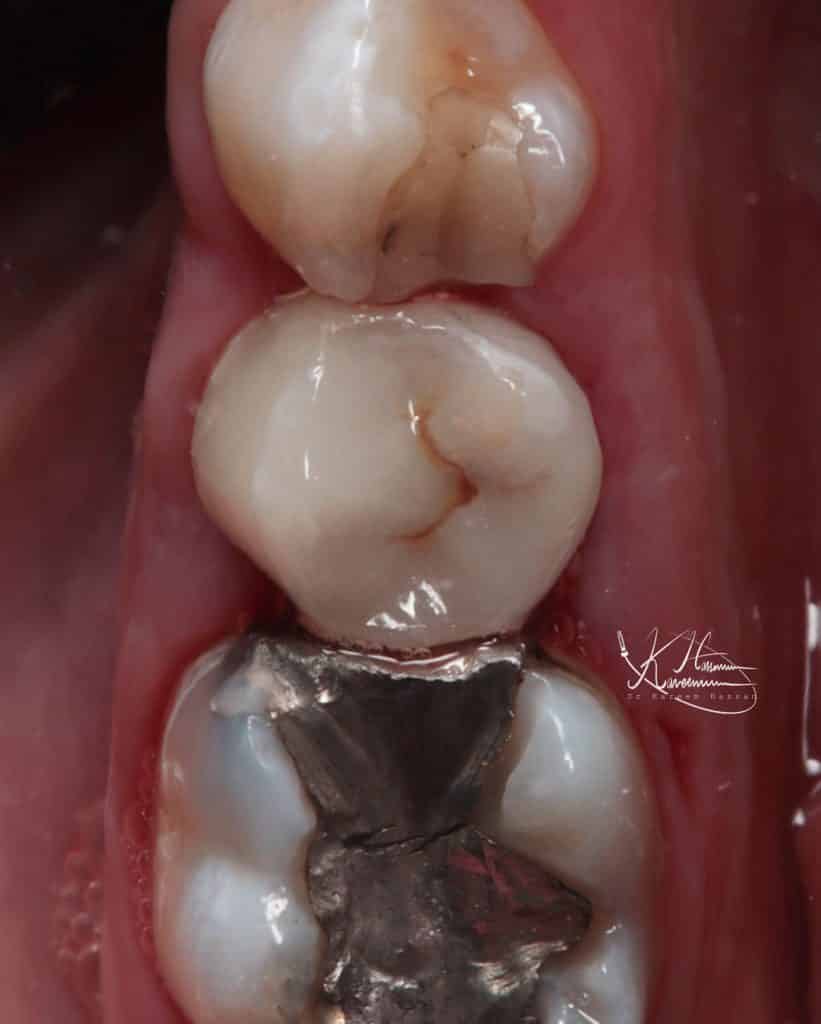

Cementation with heated composite ap-x

Final result

Buccal view